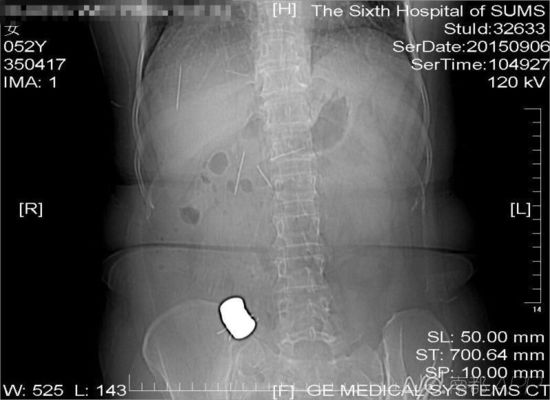

CT檢查結(jié)果中顯示,老人腹中有多個(gè)金屬異物和散落的繡花針

進(jìn)行的CT檢查結(jié)果顯示,黃姨腹中有多個(gè)金屬異物和散落的繡花針。主管醫(yī)生黃俊博士介紹,這些針?lè)謩e位于黃姨小腸內(nèi),部分已經(jīng)穿出小腸散播于腹腔內(nèi),還有部分金屬異物,最大的一塊上附著了數(shù)根斷針,有一根插進(jìn)了胰腺,剩下的一根在脊柱附近,每枚約長(zhǎng)4厘米。